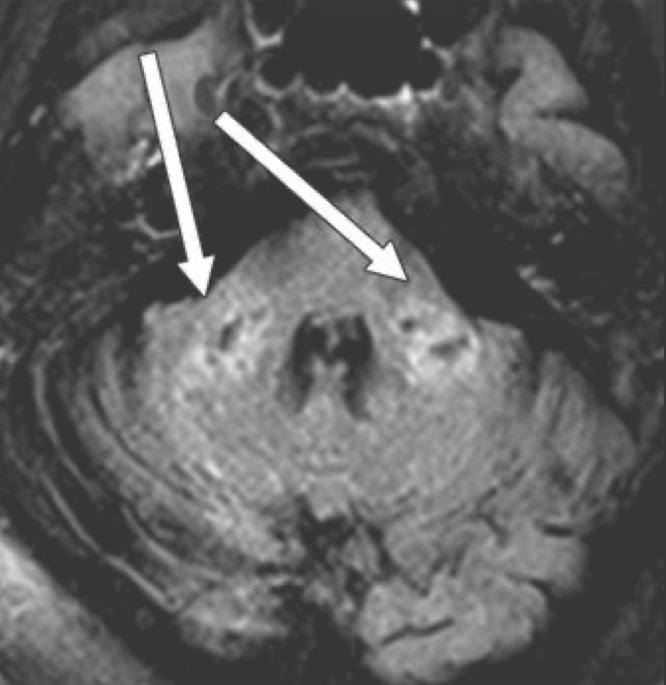

First brain MRI findings reveal dangerous COVID-19-related optical findings.